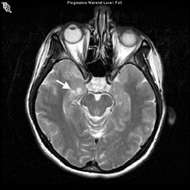

- The diagnosis is usually suspected on a magnetic resonance imaging (MRI) scan.

- Confirmation requires biopsy and resection